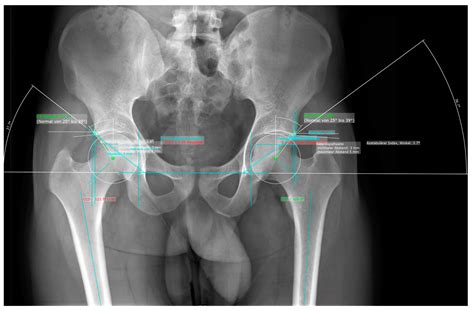

Radiologists use specific measurements and comparisons to assess the hip joint. For example, the Sharp angle and the center-edge angle are commonly used to evaluate the acetabular coverage of the femoral head. These angles help determine if the hip joint is properly aligned and functioning correctly.